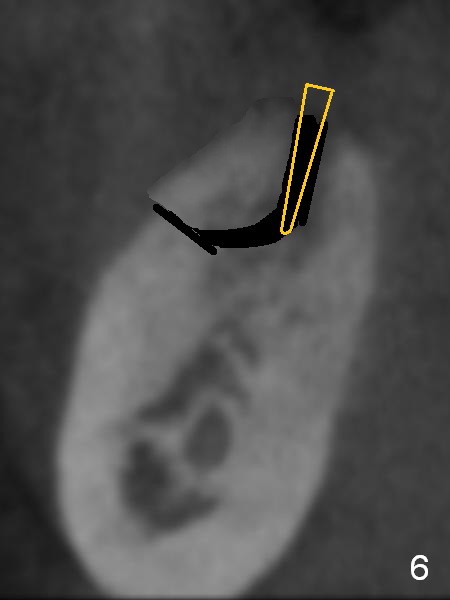

To preserve the coronal buccal plate, a two-staged ridge split will be performed. At the 1st stage, the ridge is to be sectioned as shown in red lines in Fig.5. Two to three weeks later, a chisel or bone expander will be used to pushed the sectioned segment buccally (Fig.6 yellow). As the osteotomy increases in depth and diameter and the implant as mentioned above (Fig.4) is placed (Fig.7 green), the segment is being pushed further, while it is still contacting the implant. One of the opposing dentition, #3 also needs implant.